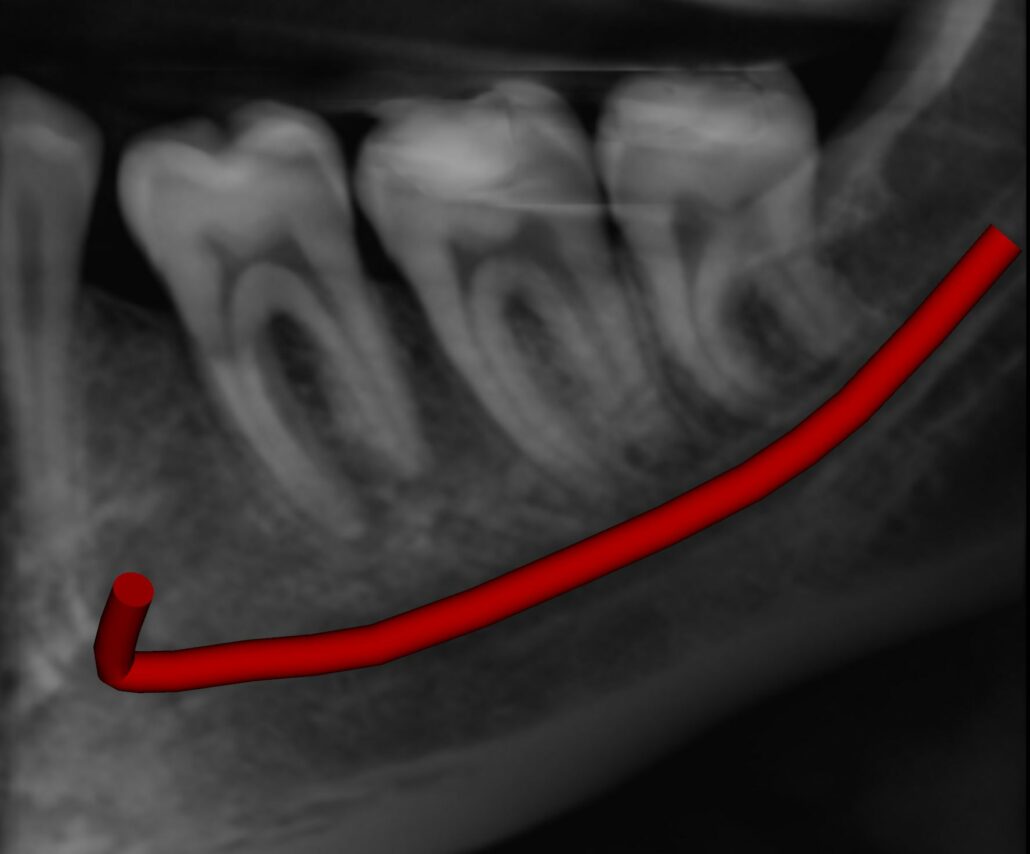

The LL8 roots have a marked distal dilaceration/apical hooks. The upper border of the inferior dental canal contacts the inferior surface of the LL8 roots.

Image 1: Reconstructed Panoramic Image